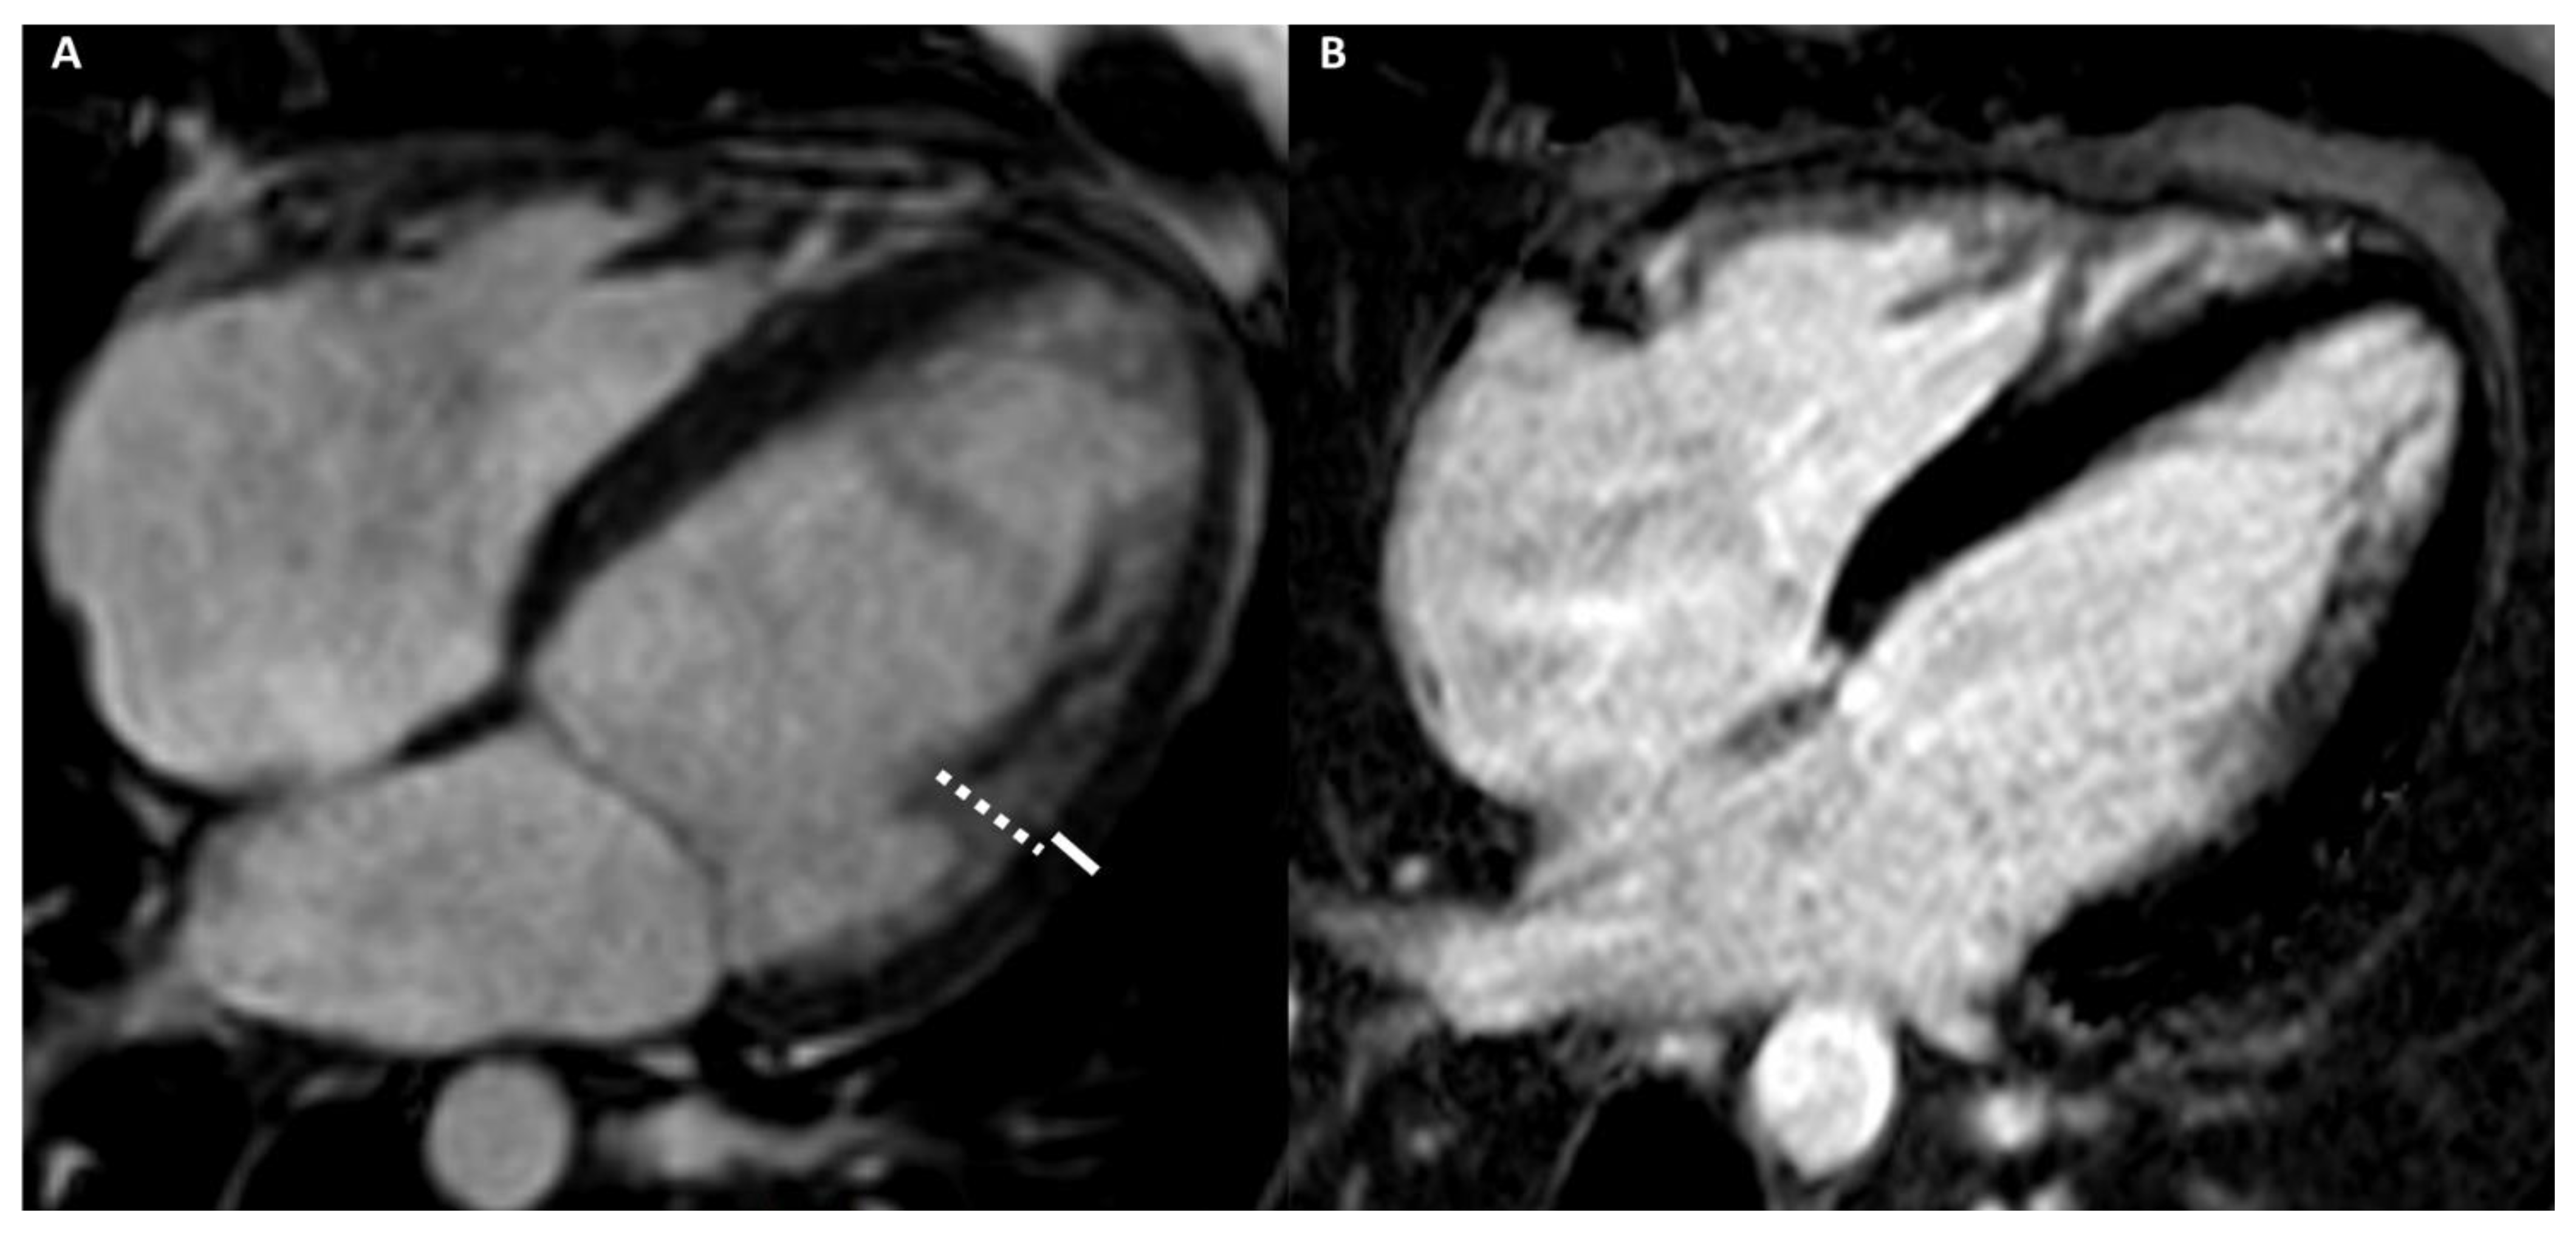

4.2.2. Cardiac Imaging: AH vs. Dilated Cardiomyopathy

4.2.3. Cardiac Imaging: AH vs. Left Ventricular Non-Compaction

4.2.4. Cardiac Imaging: AH vs. Arrhythmogenic Cardiomyopathy